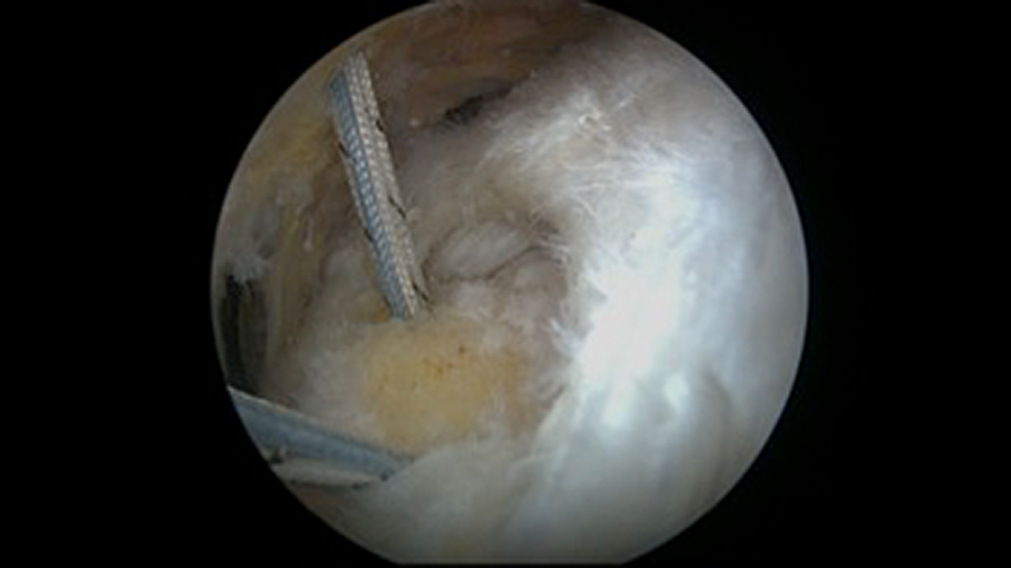

Single-Row Repair With Triple-Loaded Anchors

Single-row rotator cuff repairs were performed by placing several metal 5.5-mm corkscrew suture anchors (Arthrex) loaded with three No. 2 FiberWire sutures (Arthrex). Suture anchors were placed at the most lateral aspect of the greater tuberosity to which the tear would mobilize. Either 2 or 3 triple-loaded suture anchors were utilized to repair the tendon. A mean 2.2 anchors were used for the posterosuperior component of the repairs. Sutures were passed as simple stitches in an anterograde fashion, taking an approximately 1.5-cm bite of tissue with each stitch. All stitches were tied with 2 half-hitches on the same post, followed by another half-hitch in the alternate direction on the same post and by 3 half-hitches in alternating directions and alternating posts (Figures 3 and 4). Schematics for both repairs are shown in Figure 5. All subscapularis repairs were upper rolled border tears fixated with a single-row technique with a single anchor and 3 simple stitches.

Full-thickness supraspinatus tear viewed from the lateral portal.

Arthroscopic single-row rotator cuff repair with triple-loaded anchors and simple stitches in which 3 sutures (blue, white, and striped) can be seen originating from the same anchor.